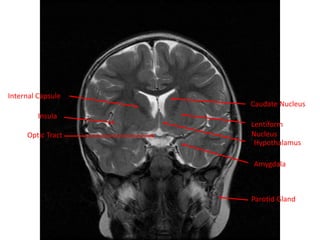

Internal Capsule

Caudate Nucleus

Optic Tract

Insula

Lentiform

Nucleus

Parotid Gland

Amygdala

Hypothalamus

Internal Capsule Caudate Nucleus OpticTract Insula Lentiform Nucleus Parotid Gland Amygdala Hypothalamus

• 68.

Internal Capsule Cingulate Gyrus OpticNerve Nasopharynx Internal Carottid Artery Lentiform Nucleus Caudate Nucleusa